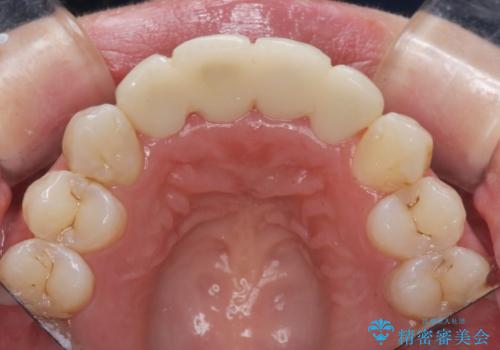

仮歯のまま放置していた前歯をセラミックに

- 仮歯のまま放置してしまい、変色を改善しきれいなセラミッククラウンをいれたい、と希望され来院されました。

特に虫歯の再発や神経の症状等問題を認めなかったので、審美的に優れるセラミッククラウンに仮歯を置き換えていきます。

- 52.8万円(ジルコニアクラウン×4・仮歯×4)費用は治療当時の料金となります

セラミッククラウンは長期的に変色しづらく、汚れのつきにくい審美製を長期的に保つことのできる治療方法です。